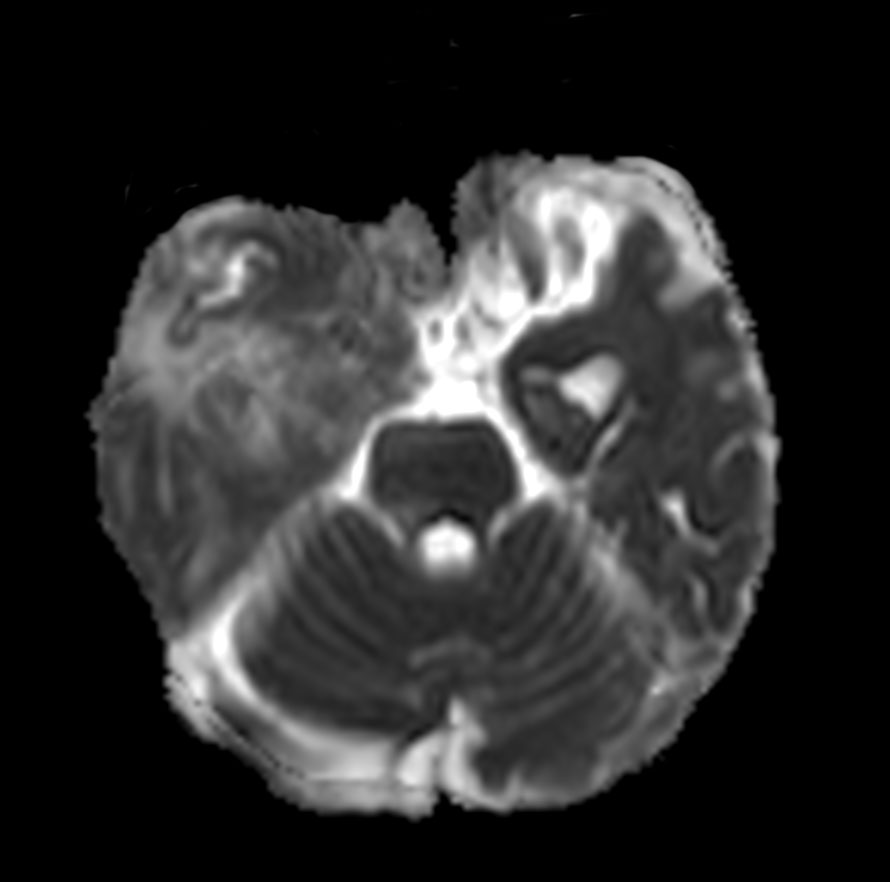

Axial DWI (b1000)

Axial DWI (ADC)

Patient with a history of astrocytoma. MRI scan requested post radiotherapy treatment. Diagnosis: Recurrent neoplastic disease.